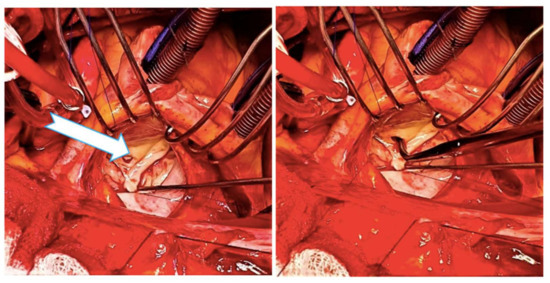

2. Case Report